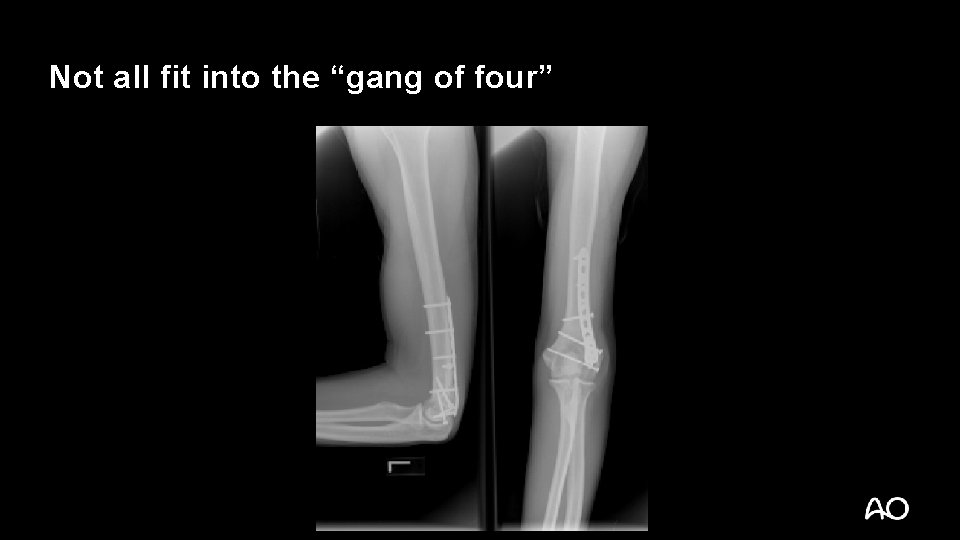

Not all fit into the “gang of four”

Be on the lookout for combined injuries